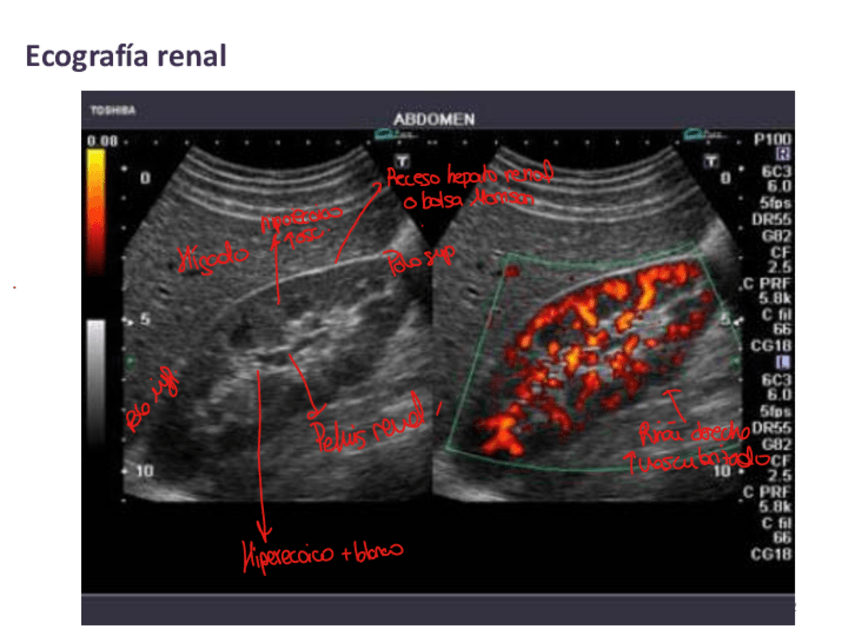

He publicado nuevos examenes de 2º Aparatos Digestivo y Genitourinario: EXAMEN-GENITOURINARIO-2019.pdf

11 páginas